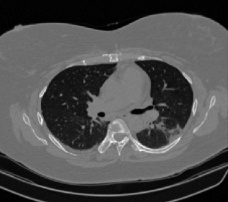

It should be mentioned that for explainability purposes [7, 8, 9], an anchor set was generated for the COV19-CT-DB database [5]. This included 11 anchors, each representing a respective 3-D CT scan obtained through an appropriate clustering procedure. Figure 2 shows a series of slices from a COVID-19 case, whereas Figure 3 shows a series of slices from a non COVID-19 case.